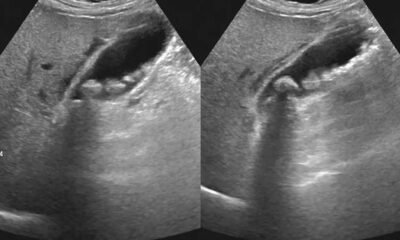

Reddit user NovellaJokes recently asked, “Women of Reddit, what’s something they never tell us about pregnancy and childbirth?” Here are the fascinating, terrifying, and downright brutal...